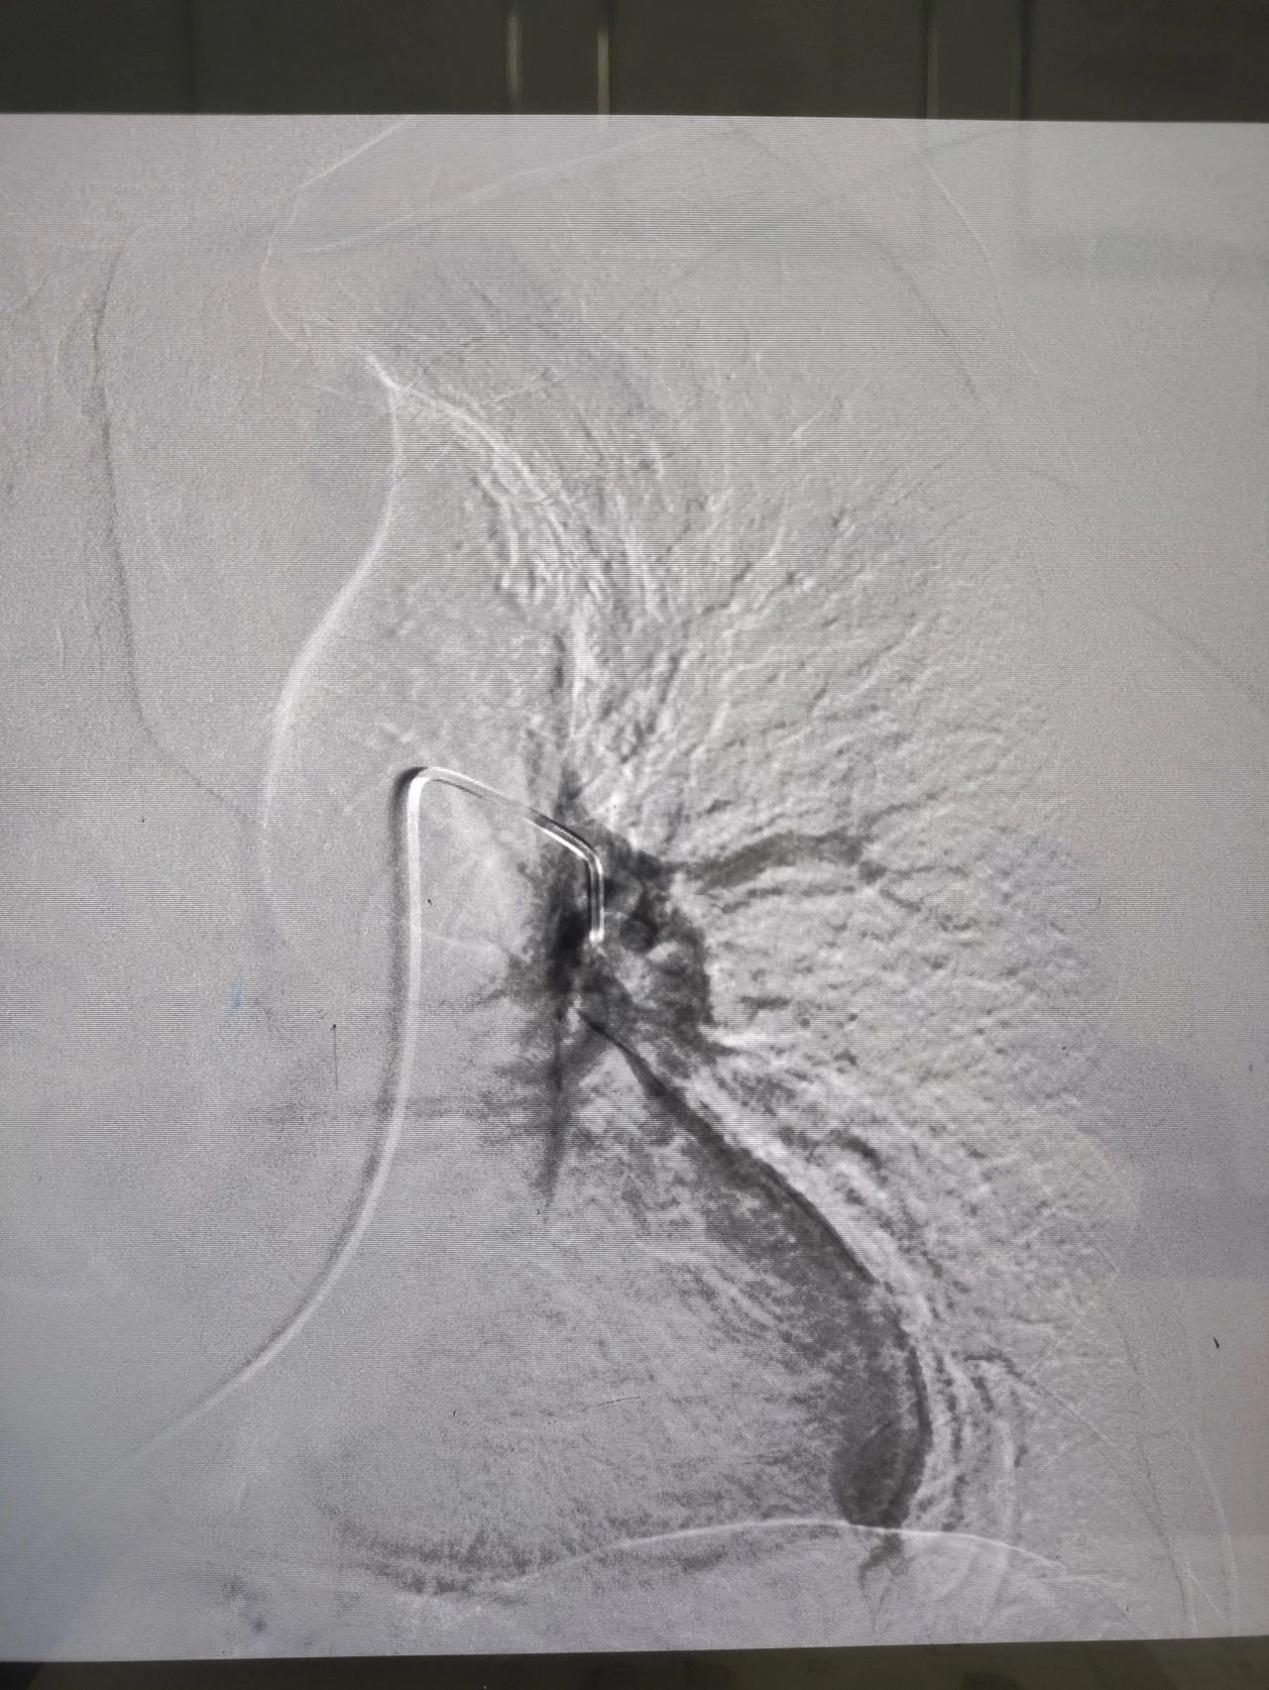

患者男性,69岁,2024年8月12日以“右侧下肢肿胀1周”在综合外科二病区就诊,后以“右下肢深静脉血栓形成”积极收住院治疗。次日查房时发现,患者血氧过低(约60%),我科援藏专家谢文涛主任考虑患者存在肺栓塞可能,立即主持科内术前讨论后建议立即行肺动脉造影介入治疗。经过40分钟的紧急手术治疗,左肺动脉主干血栓完全清除,为预防后期再次出现肺栓塞,同时下腔静脉置入可回收滤网。患者自身症状明显缓解,患者及家属对治疗效果非常满意,并于两周后,8月28日再次入住综合外科二病区,顺利取出可回收滤器。